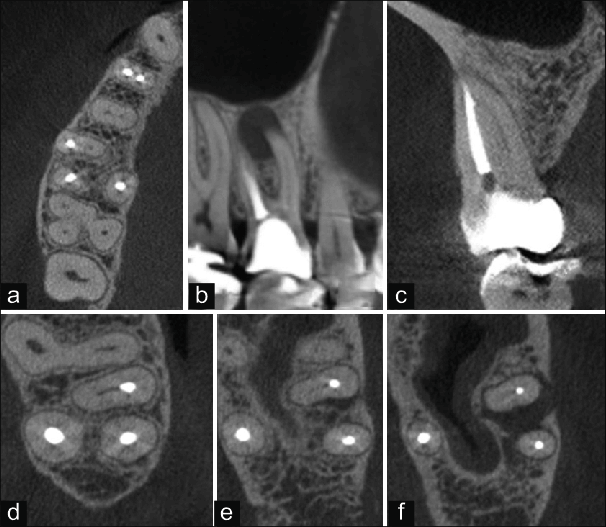

At Champions for Oral Health, CBCT imaging is used to guide root canal diagnosis and treatment planning. It gives us a precise, three-dimensional view of the tooth, canal system, and surrounding bone that a flat X-ray simply cannot provide.

Identifies all canals — including hidden accessory and lateral canals missed on 2D X-ray

Precisely maps canal curvature and length before a single instrument enters the tooth

Detects the full extent of periapical infection and bone involvement

Identifies root fractures, resorption, or anatomical complications pre-operatively

Confirms healing after treatment at follow-up review

Missed canals are the most common cause of root canal failure. CBCT imaging eliminates the guesswork — giving us the full picture before treatment begins, and giving patients a better chance of long-term success.

Standard 2D dental X-rays have significant limitations when it comes to root canal diagnosis. They compress a three-dimensional structure into a flat image — missing hidden canals, obscuring bone involvement, and failing to show the full extent of infection in many cases.